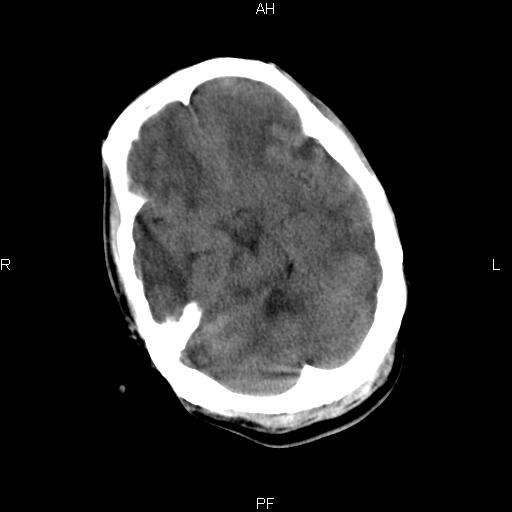

男性,45岁,缄默少语,四肢无力一个月。骨窗未见明确异常。

弥漫性脑白质低密度症

对称性脑白质广泛低密度。有高血压史及大量饮酒史吗?

考虑重度脑白质稀疏症。

双侧弥漫性对称性全累及性(外囊亦有累及)脑白质病

患者病程月余,脑沟裂闭合,第三脑室较窄,提示应该有较明显的脑白质水肿,考虑有持续性炎性病变

综合考虑脑白质感染性或非感染性炎症可能性大,不排除为克雅氏病